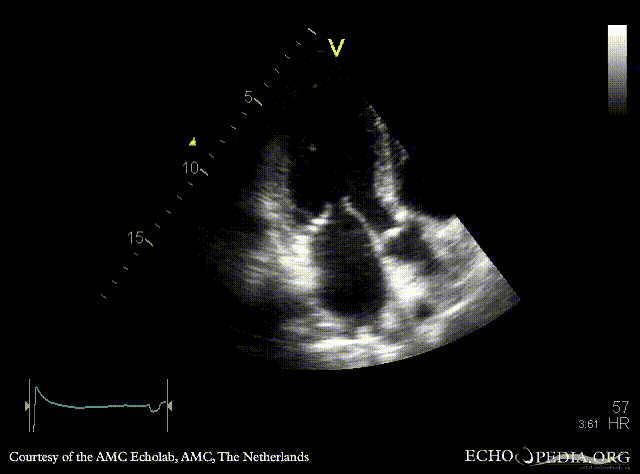

Diastloic dysfunction (pseudonormalisation)

A4CH: normal systolic function of left ventricle A2CH